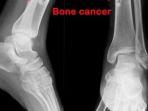

Selain nyeri tekan, di sekitar area yang terkena kanker bisa bengkak dan merah